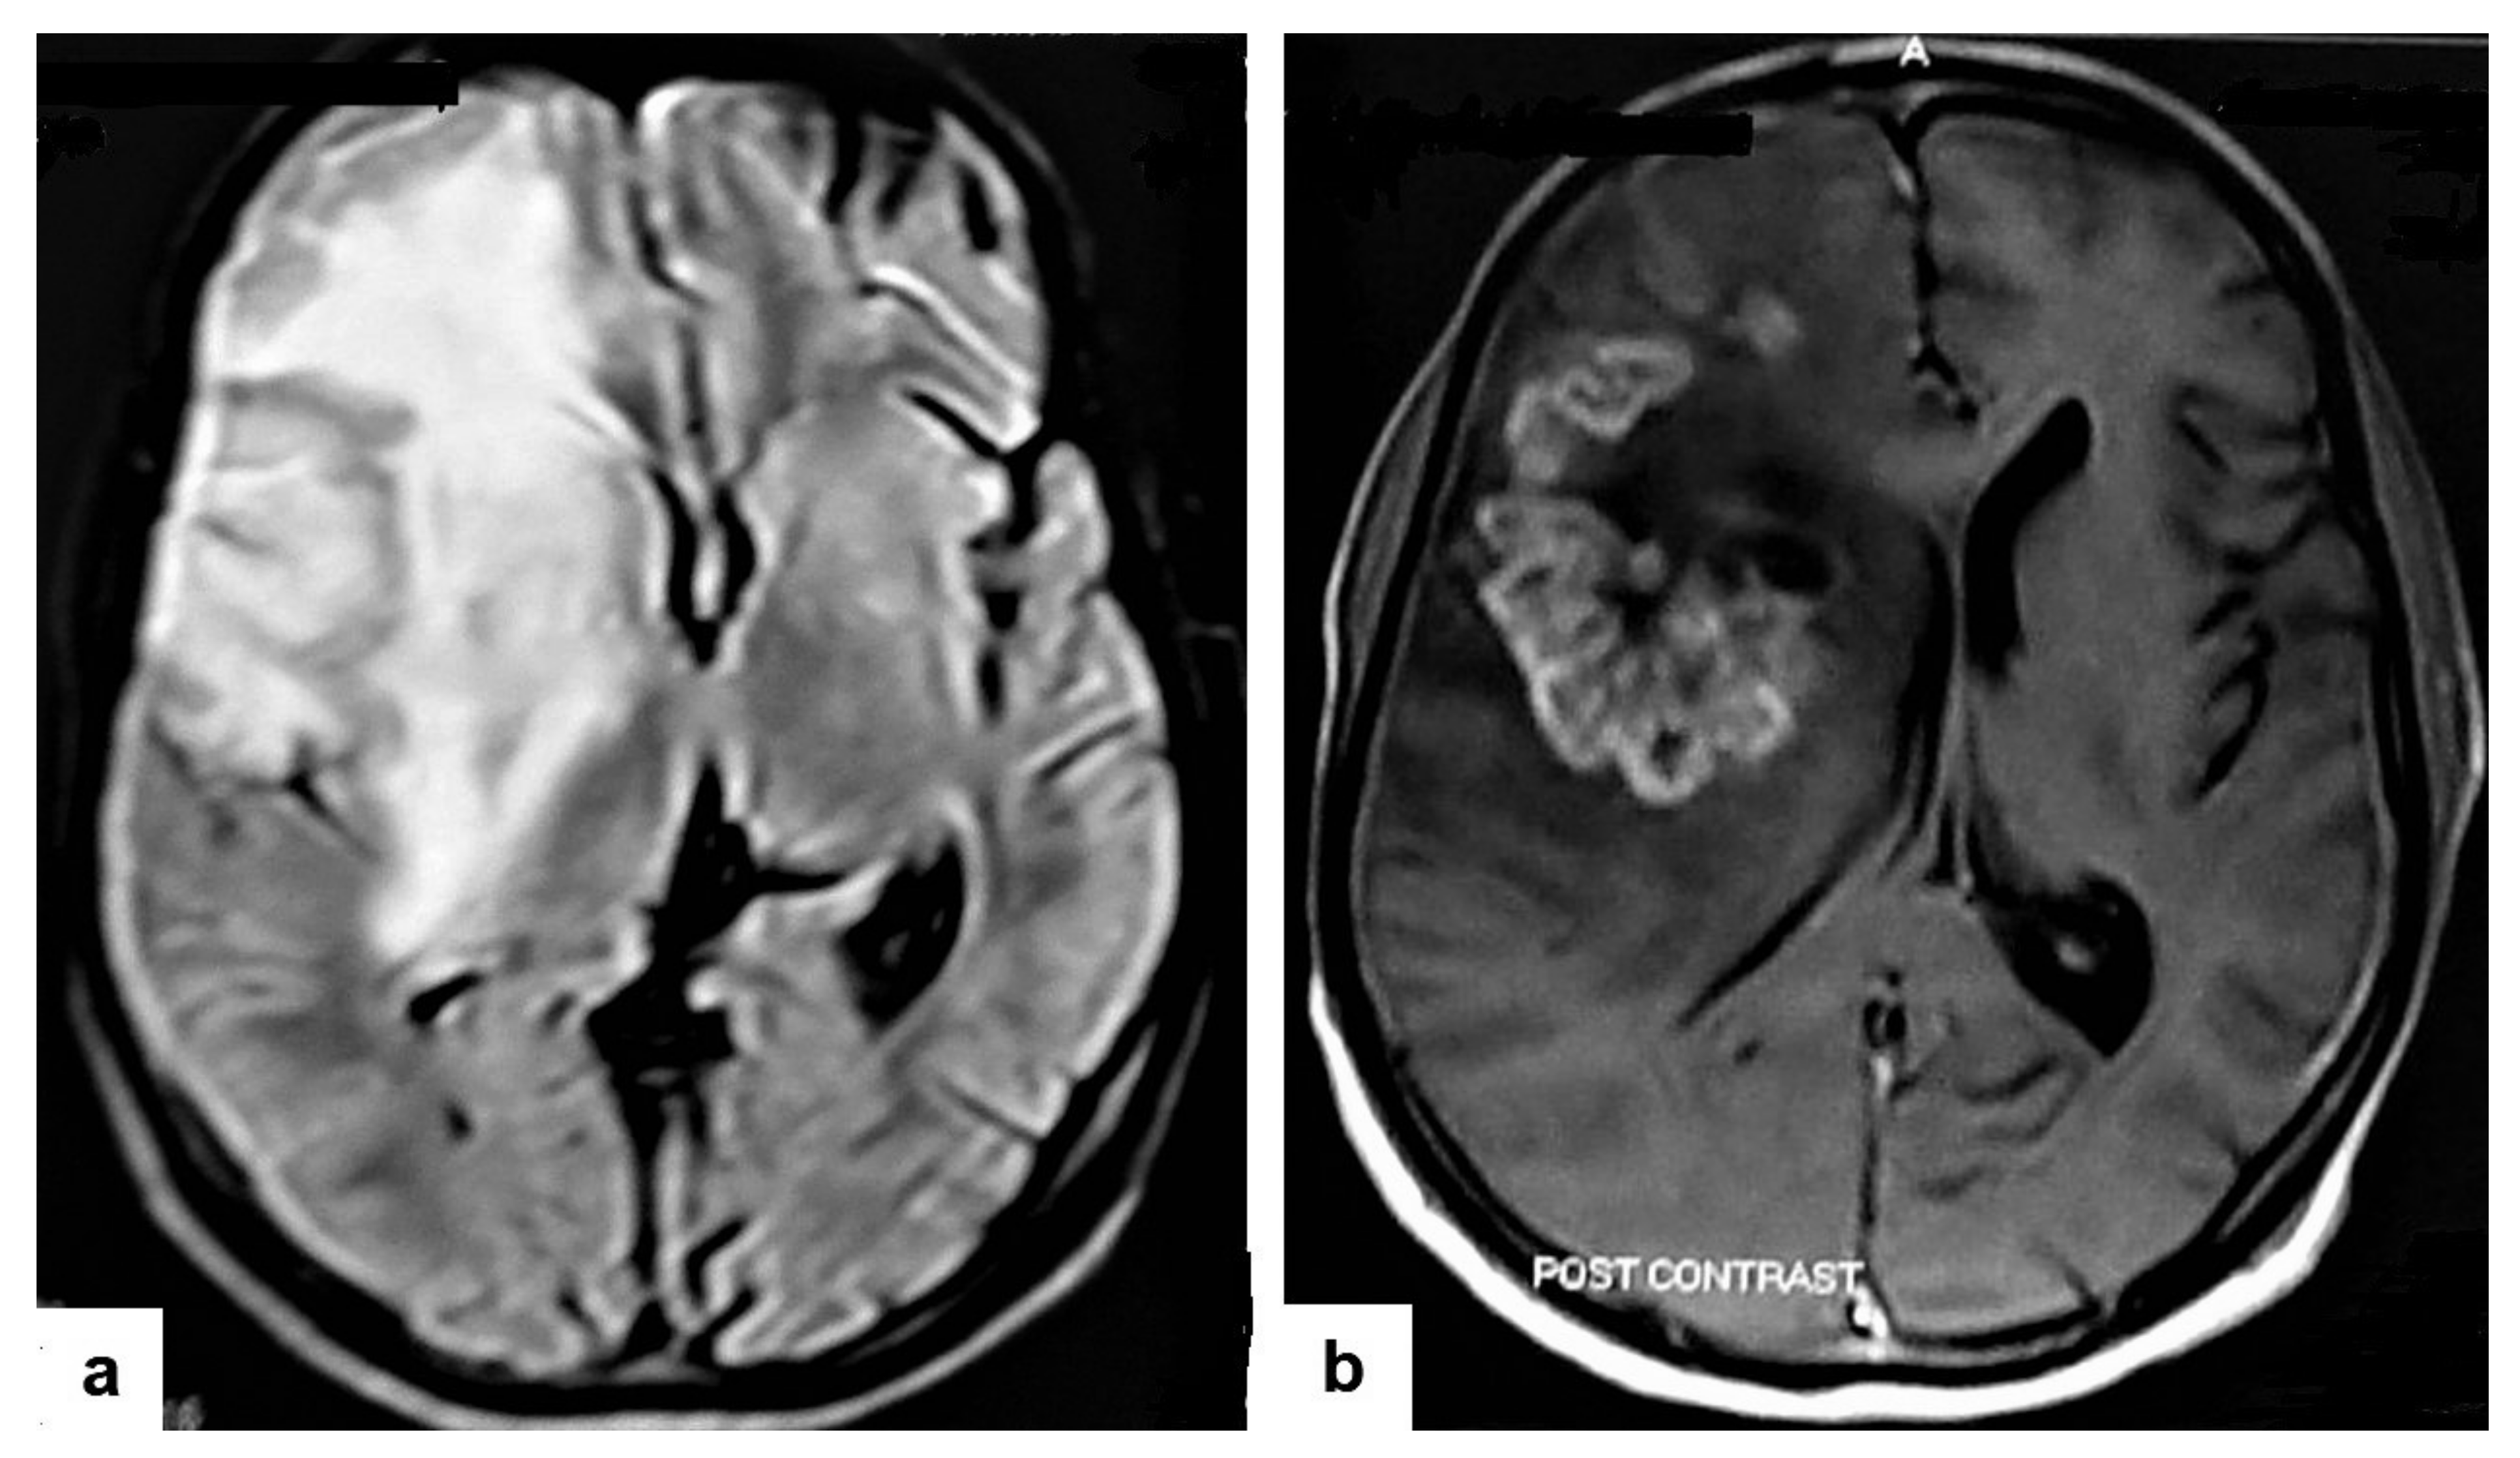

• Tuberculous cerebritis (Figure 14) is an infection of a focal area of a brain parenchyma that appears on MRI as an area of swelling with an alteration to the signal intensity of the gyri. The involved gyri appear with a low signal intensity on T1WIs and high signal on T2WIs with patchy enhancement after contrast administration [25,26]. Neuroimaging using a CT and MRI plays a crucial role in early diagnosis and avoids the worst complications of cerebritis. Tuberculous cerebritis is characterized by a small tuberculous granuloma and appears as intense areas of patchy enhancement with edema which mimics infarction those can be differentiated by diffusion-weighted MRI [32].

Figure 14. Tuberculous cerebritis in an adult man with fever and seizures. (a) Axial FLAIR-weighted images of brain MRI show high signal intensity in the right parietal and frontal lobes causing mass effect compressing the right lateral ventricle with mild shifting of the midline to the contralateral side. (b) Axial brain T1-weighted images post-contrast administration show intense serpentine (gyriform) enhancement in the right parietal and frontal lobes, with significant surrounding edema, suggesting tuberculous cerebritis.